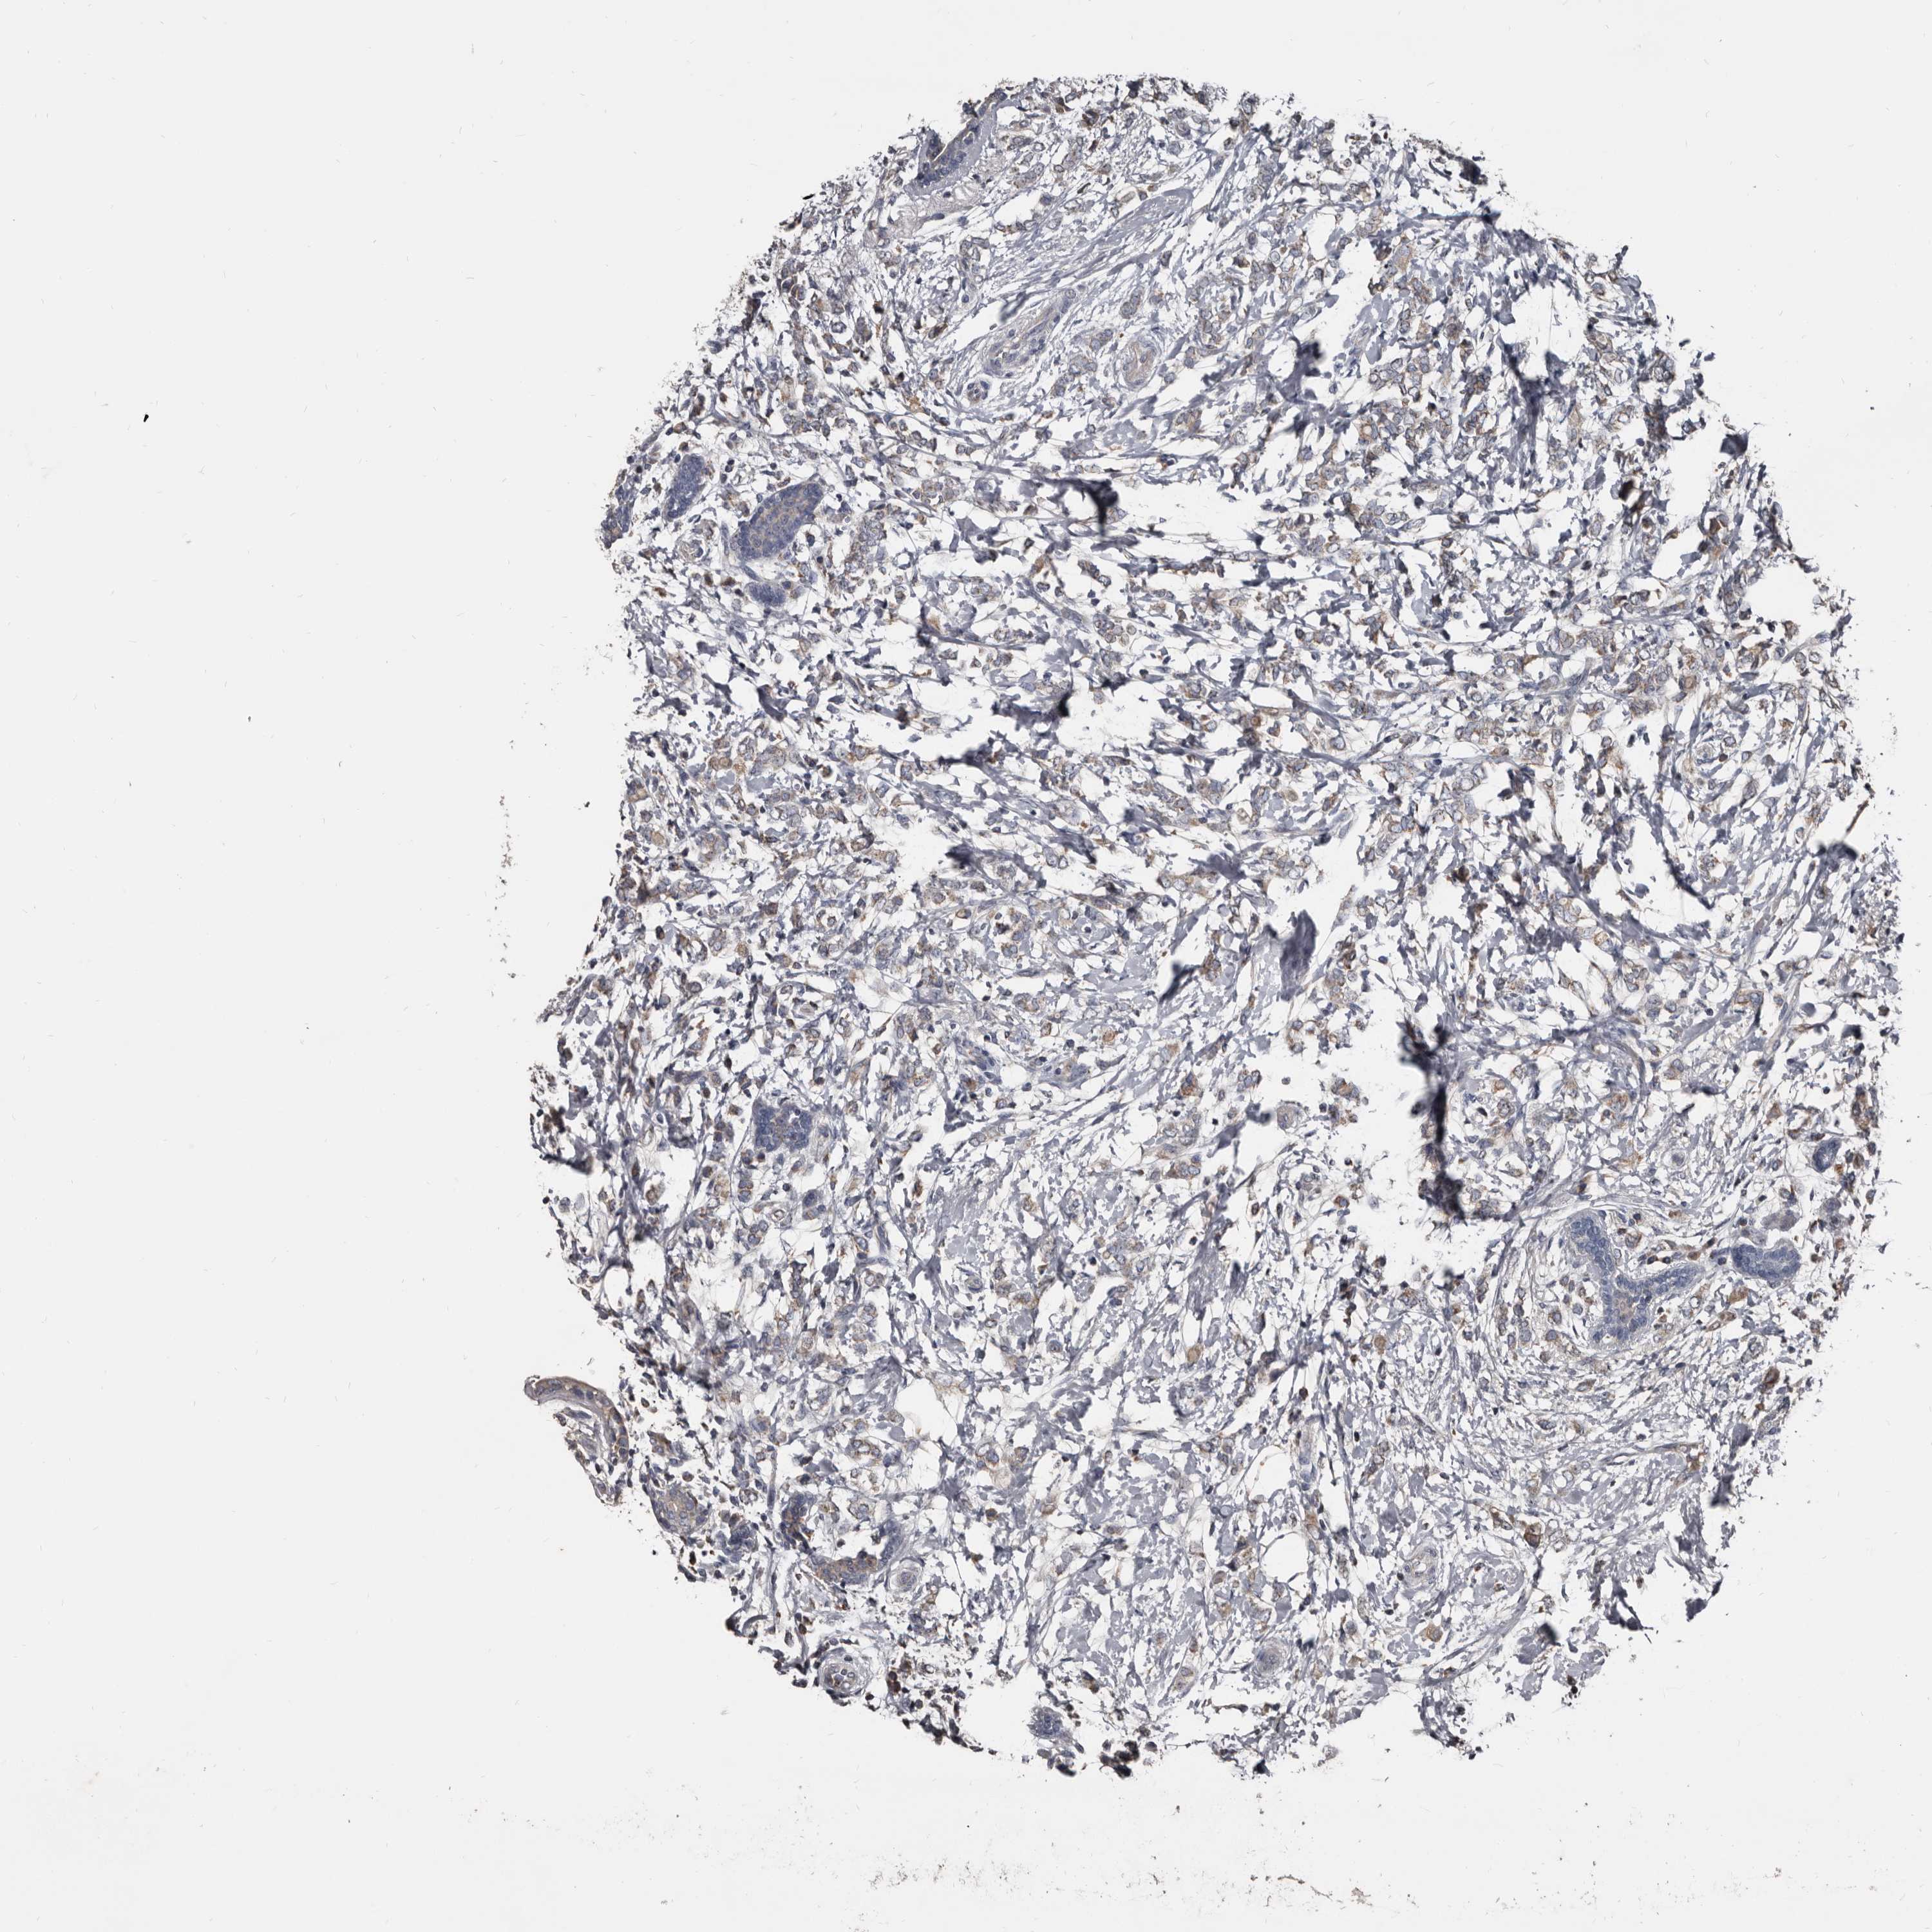

CANCER BREAST CANCER Show tissue menu

BRCA TCGA BRCA VALIDATION PROTEIN EXPRESSION